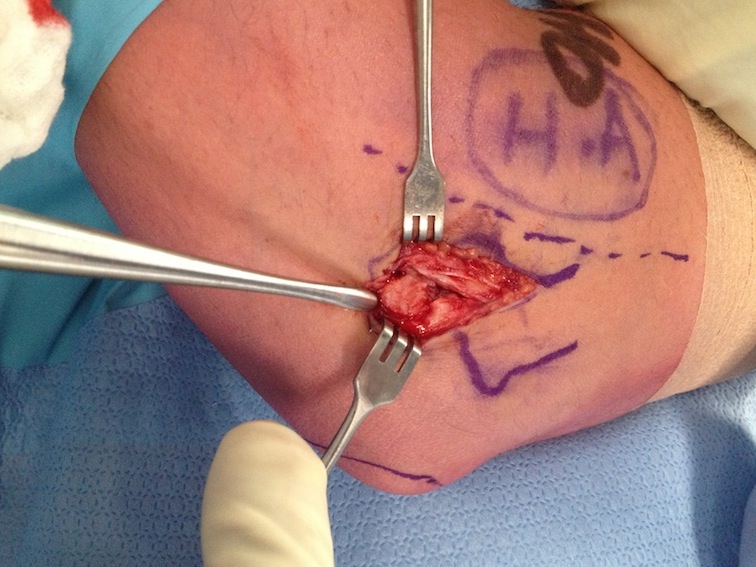

Open tennis elbow release

Technique

Incision centered on common extensor origin

- slightly anterior to radiocapitellar joint

- elevate ECRL (ECRL muscular at this point)

- ECRB is deep and posterior to ECRL

- detach ECRB from lateral epicondyle

- debride degenerative tissue and decorticate underlying common extensor origin

- +/- reattach ECRB with suture anchors